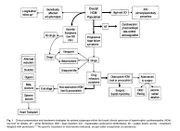

| 04:47, 1 July 2012 | Pathophysiology.JPG (file) |  |

30 KB | 1 | |